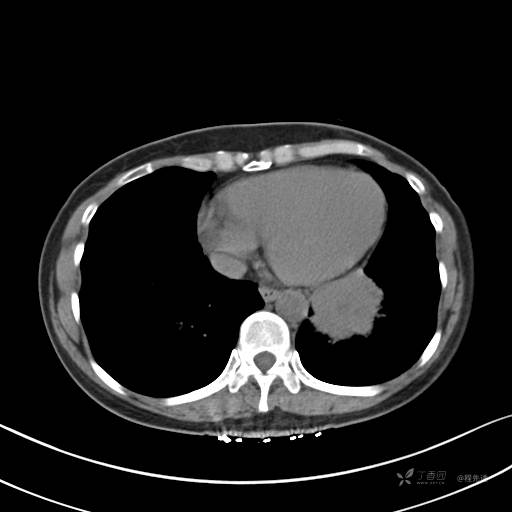

CT平扫

纵隔窗

病灶平扫CT值约31HU